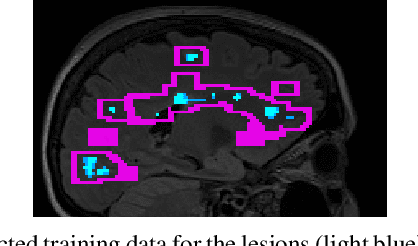

Abstract:Multiple sclerosis (MS) is an inflammatory and neurodegenerative disease characterized by diffuse and focal areas of tissue loss. Conventional MRI techniques such as T1-weighted and T2-weighted scans are generally used in the diagnosis and prognosis of the disease. Yet, these methods are limited by the lack of specificity between lesions, their perilesional area and non-lesional tissue. Alternative MRI techniques exhibit a higher level of sensitivity to focal and diffuse MS pathology than conventional MRI acquisitions. However, they still suffer from limited specificity when considered alone. In this work, we have combined tissue microstructure information derived from multicompartment diffusion MRI and T2 relaxometry models to explore the voxel-based prediction power of a machine learning model in a cohort of MS patients and healthy controls. Our results show that the combination of multi-modal features, together with a boosting enhanced decision-tree based classifier, which combines a set of weak classifiers to form a strong classifier via a voting mechanism, is able to utilise the complementary information for the classification of abnormal tissue.